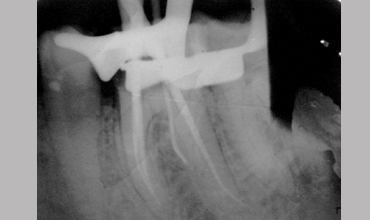

Management Of Radix Entomolaris In Mandibular First Molar